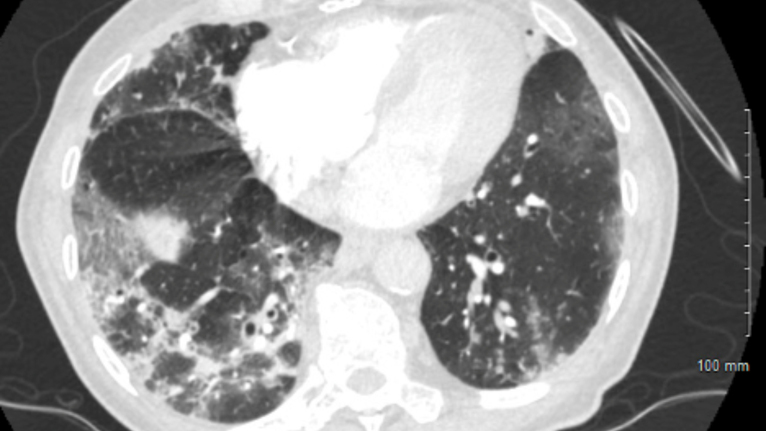

COVID-19 Lung X-Ray - 2 - Lung Damage

Figure 4 - CT chest showing multifocal ground glass opacities with intermixed consolidation from COVID-19 bronchopneumonia.